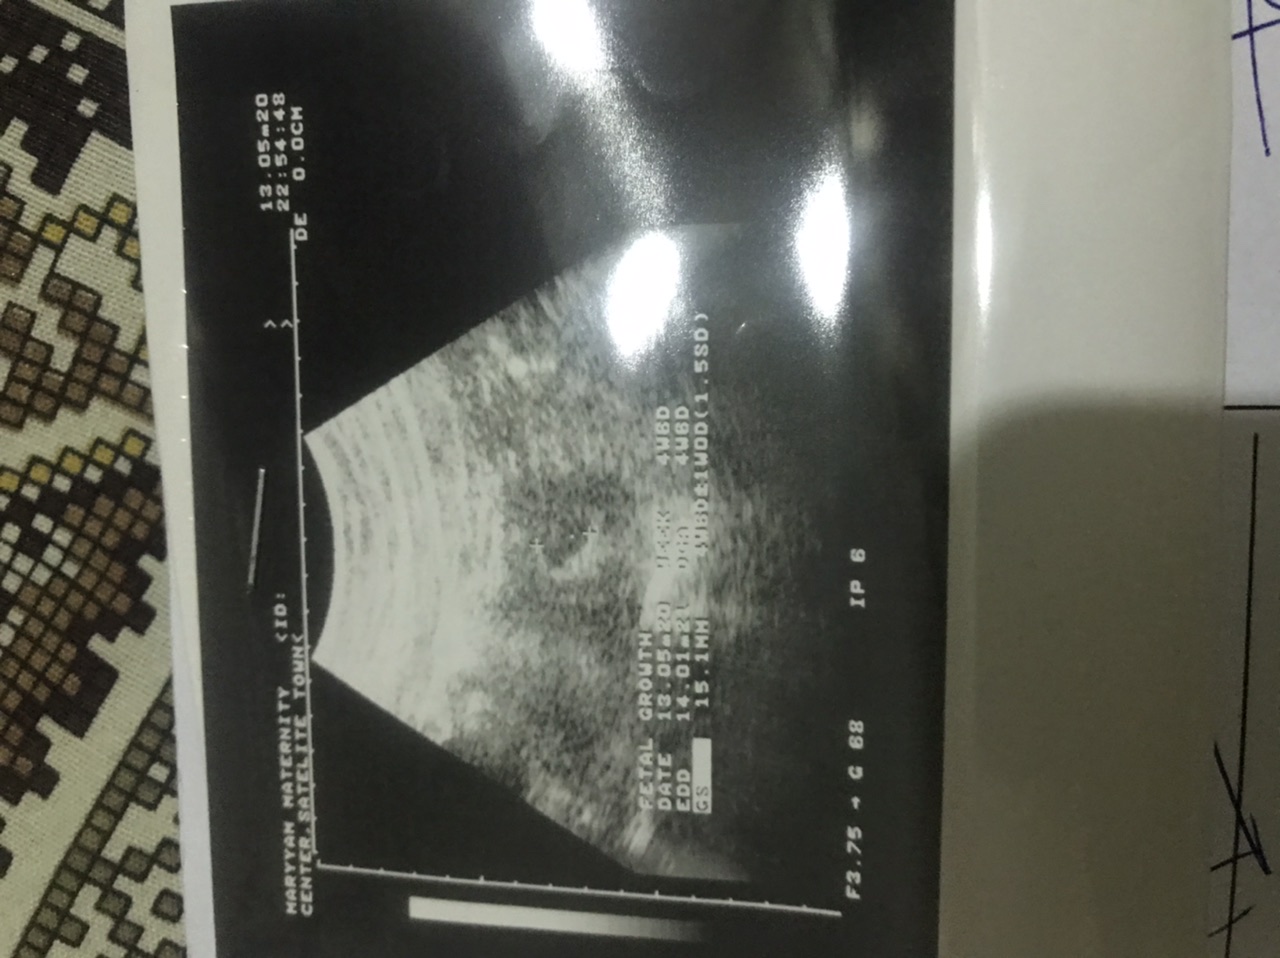

My LMP was 25th March,2020. I was having abdominal pain with backache so I went to the doctor. She performed ultrasound (note: my bladder was empty) according to her she could see only gestational sac and that shows 5 weeks pregnancy while according to my LMP It is my 6th or 7th week. She also asked me to repeat US after 15 days. My question is it normal? Or is that going towards a missed miscarriage? I'm just so tensed, its my first pregnancy

Attach Photo here: